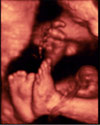

Ecografía 4D de un feto moviendo los ojos en el tercer trimestre de embarazo

La imagen ecográfica en 4D nos sorprende porque vemos a un bebé haciendo movimientos con la cara: incluso se aprecia como abre y cierra los ojos, preparándose así para la vida extrauterina.